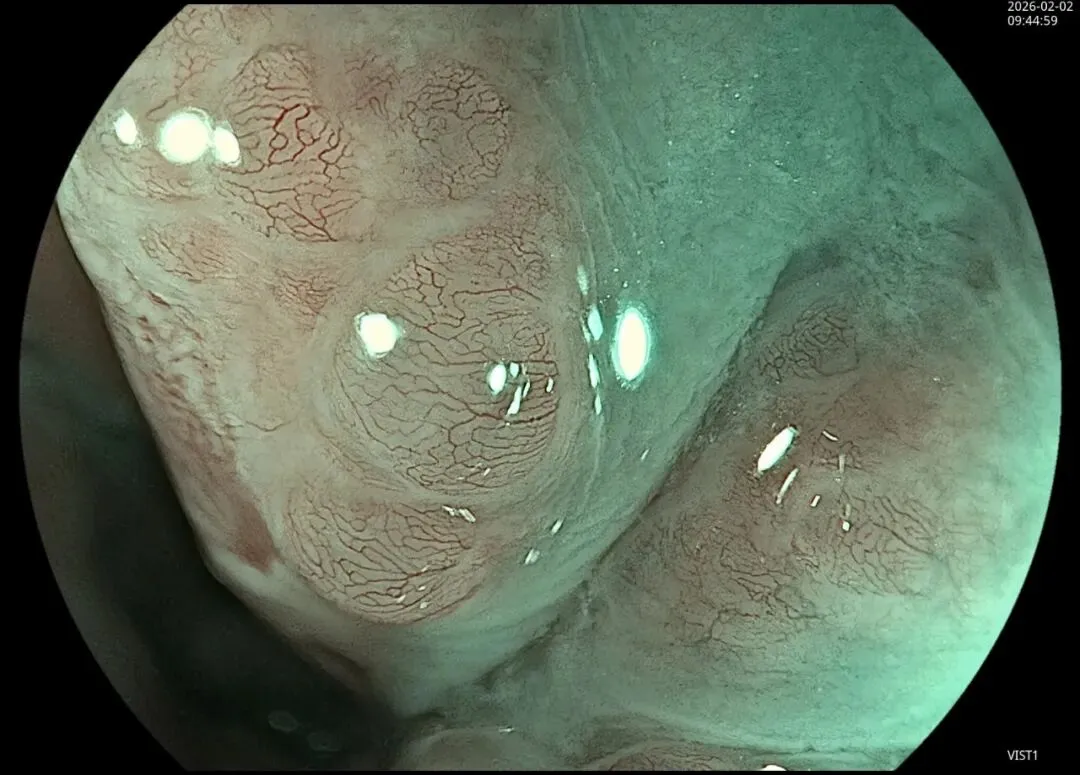

这一期不用码字,挺好的,很可惜一直没机会听过胡导讲的关于这个“花环征”的大课,学习内容来源于雨夜大师的号花环征:AIG背景的胃食管结合部的黄色颗粒状隆起及半透明“泡状”改变

补充自己在两例A型胃炎/AIG 观察到的“花环征”,巩固下学习效果。。。

case2:(made in china机子)👇

1.白光表现为胃食管交界处黄色颗粒状隆起及半透明“泡状”改变

2.窄带光下可见颗粒状隆起呈褐色改变,放大可见细微网状血管结构及半透明“泡状”改变

3.典型病理是鳞状上皮局灶性变薄及黏膜固有层显著增生、扩张的贲门腺。